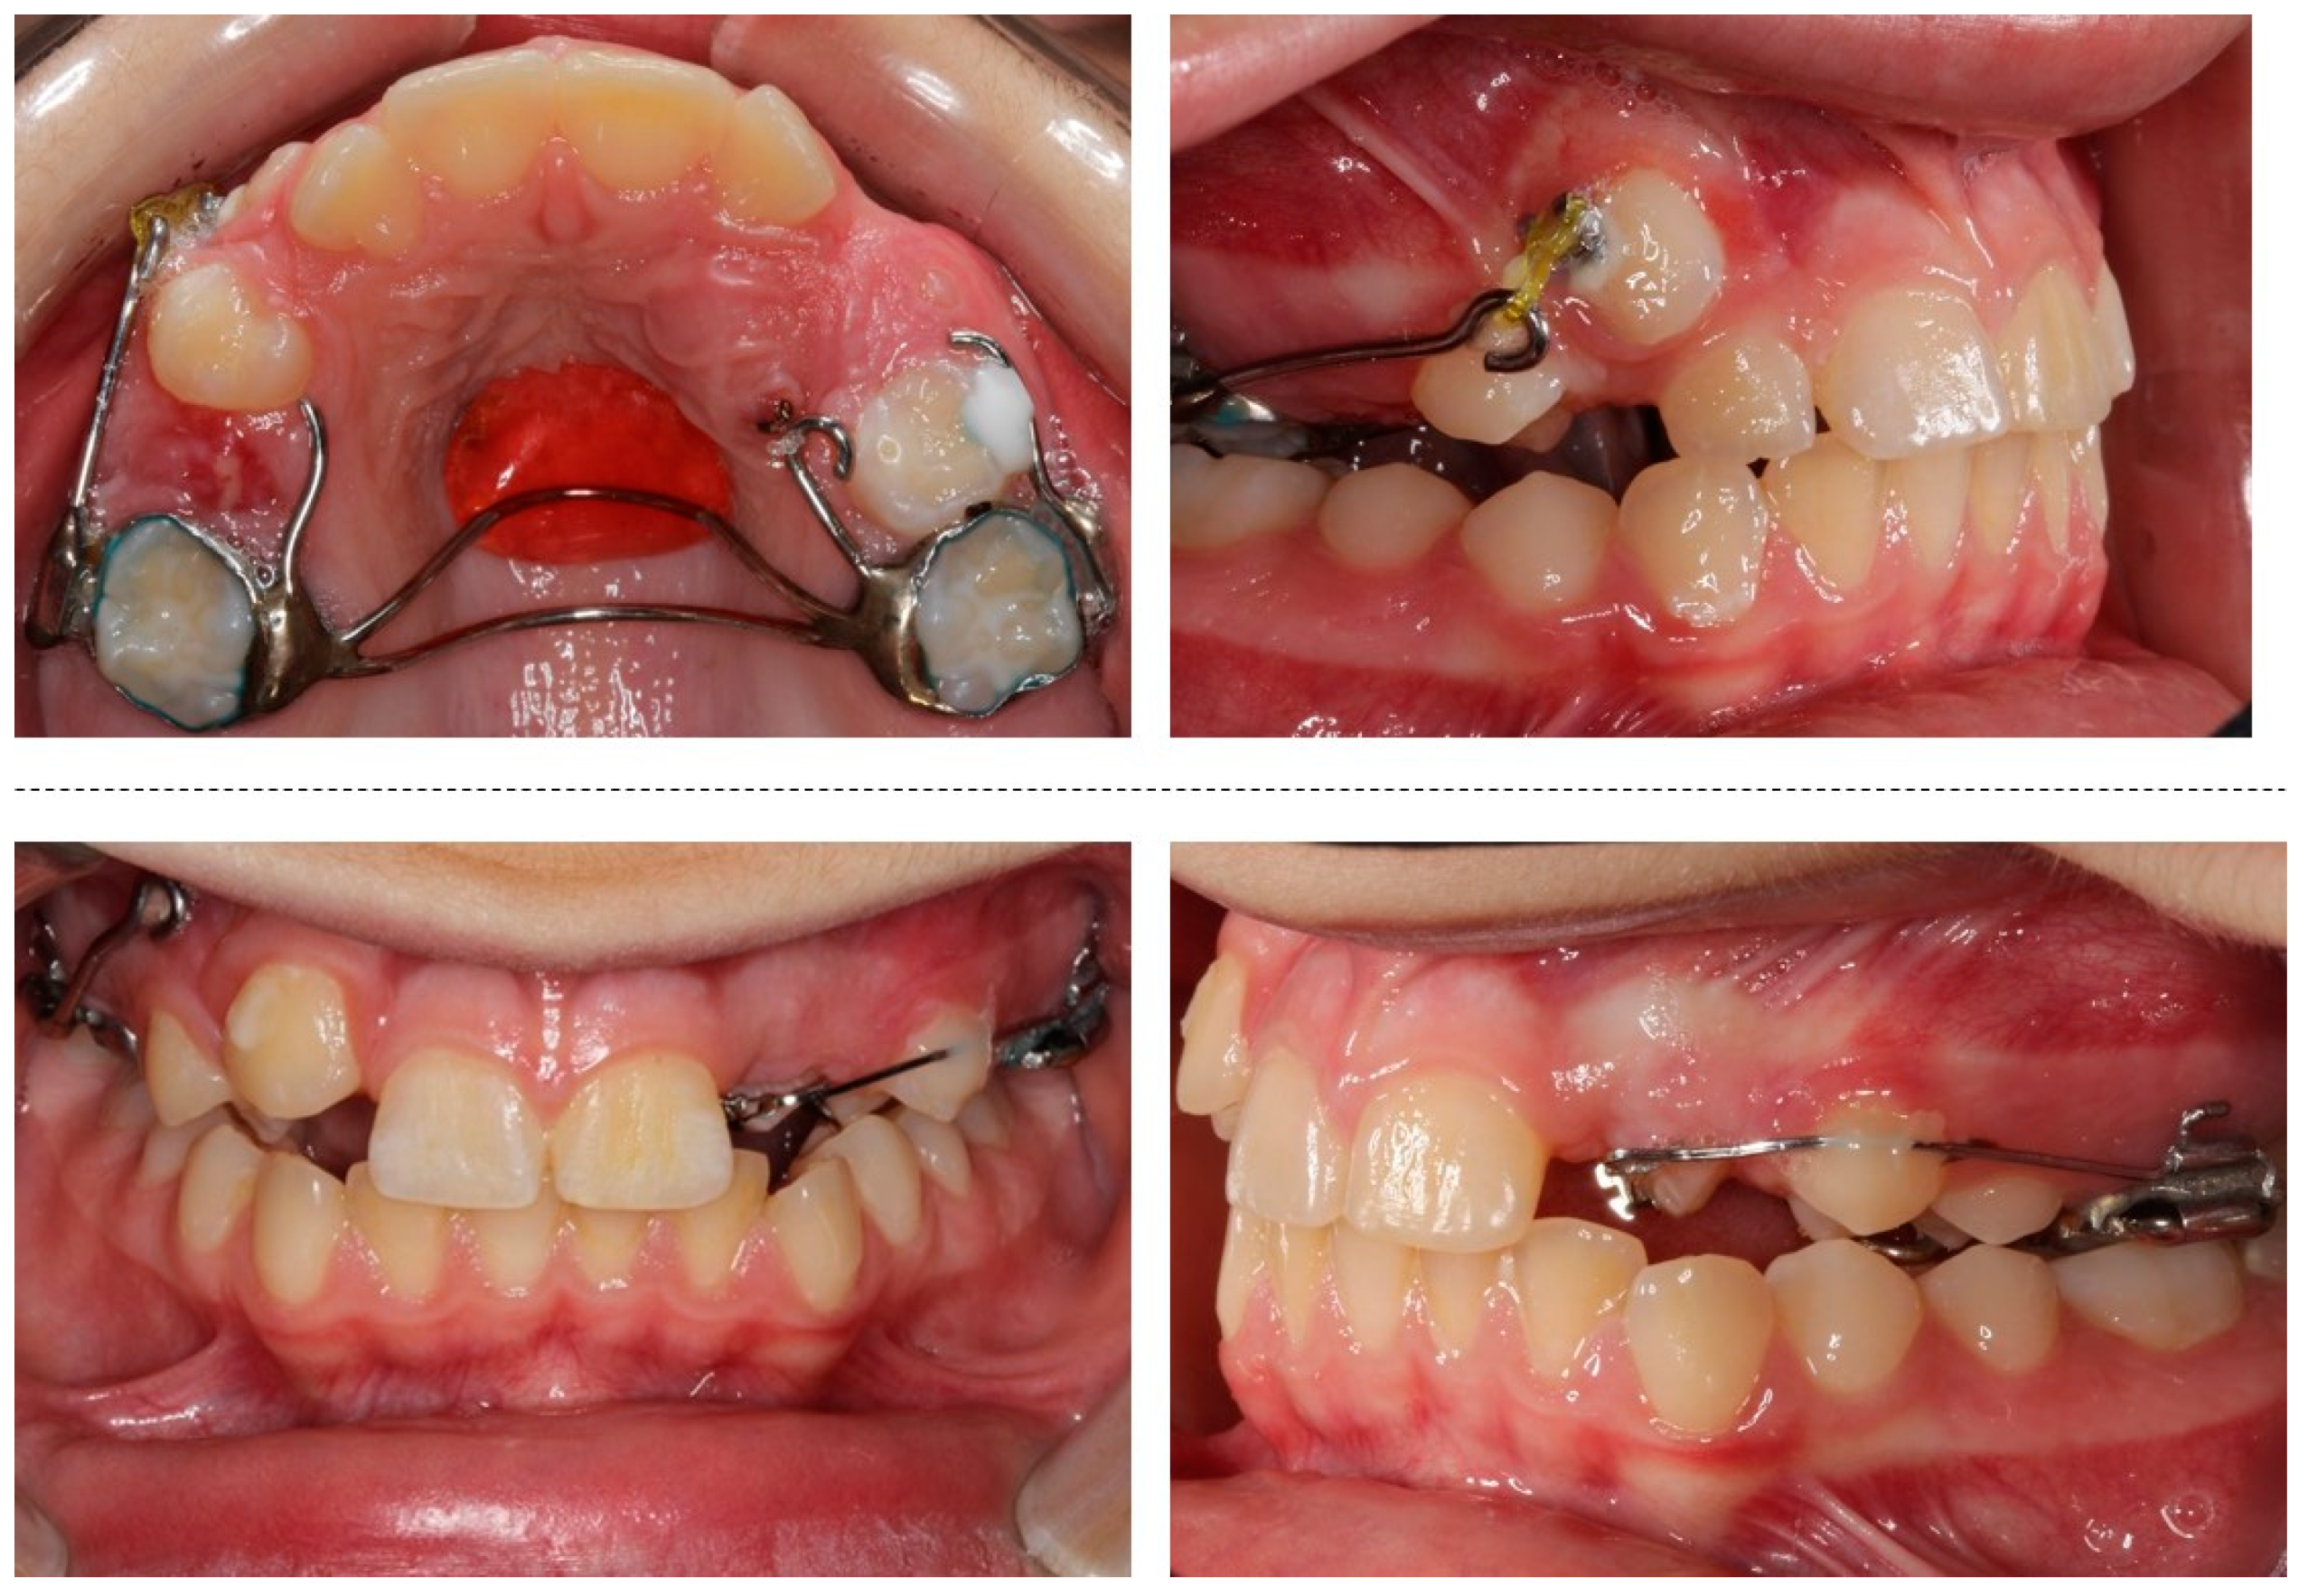

2. Case Presentation

2.1. Clinical Findings and Diagnosis

2.3. Treatment Planning

2.4. Treatment Results